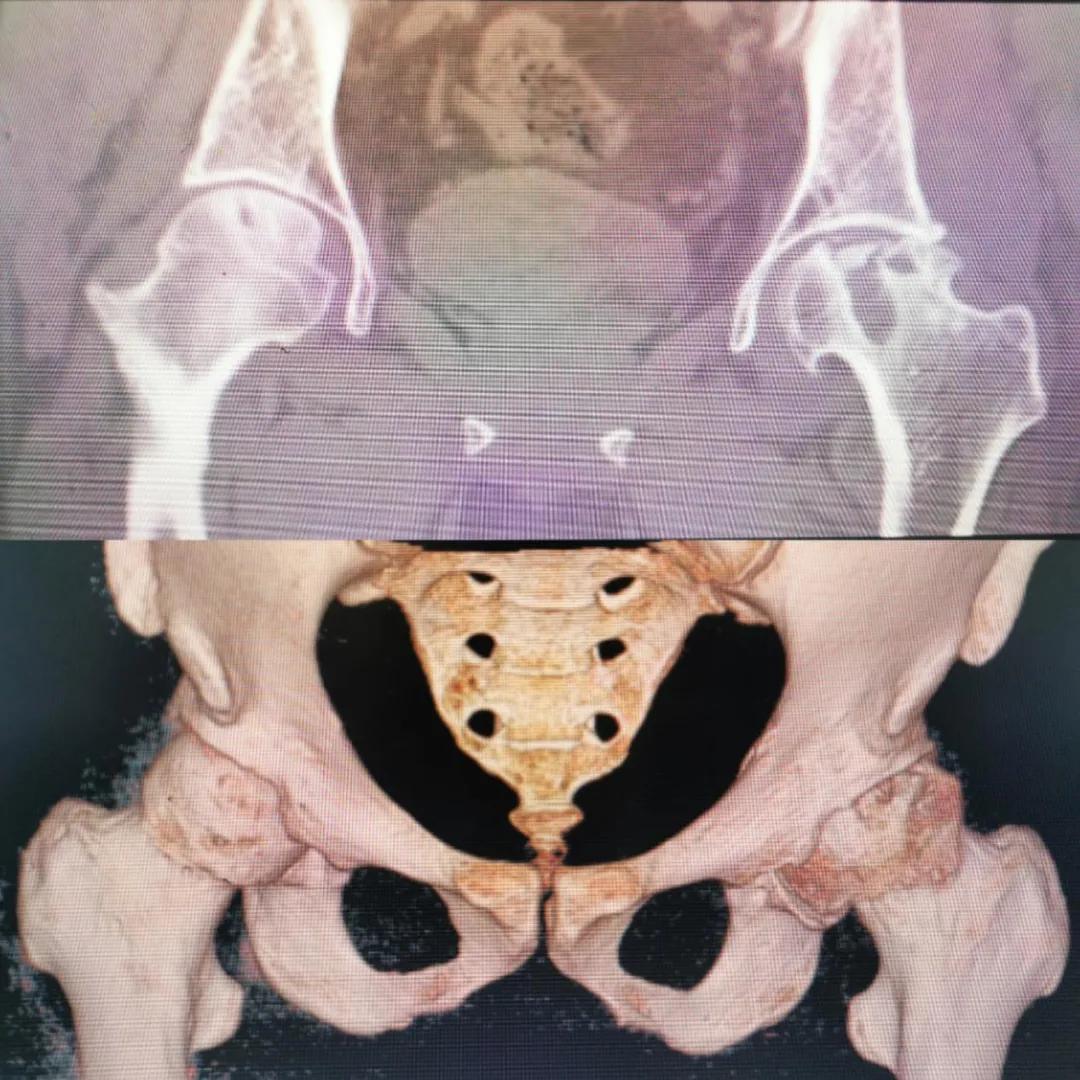

圖片(圖為患者入院時髖部CT檢查)

入院急查血結(jié)果提示炎癥反應(yīng),感染較重,凝血功能及肝功均不同程度損害;髖關(guān)節(jié)磁共振(MRI)檢查提示雙側(cè)股骨頭缺血壞死,繼發(fā)髖關(guān)節(jié)炎,左側(cè)髖周軟組織腫脹。醫(yī)療團(tuán)隊給出的初步診斷為膿毒血癥、股骨頭缺血性壞死、軟組織感染、皮膚潰瘍及閉孔神經(jīng)損傷。

追溯病史,患者訴前不久曾用蜂蜇療法治療股骨頭壞死,每日4次,每次100只蜜蜂蜇雙臀部、髖部,這才導(dǎo)致了病情急劇進(jìn)展。查明了來龍去脈,我院智能微創(chuàng)骨科醫(yī)護(hù)團(tuán)隊與患者家屬積極溝通病情,給予特殊級抗生素抗感染以及消腫、止痛等支持治療,同時對潰瘍創(chuàng)面進(jìn)行專業(yè)、規(guī)范的清創(chuàng)、換藥處理,保護(hù)創(chuàng)面降低感染程度;護(hù)理上輔助翻身,減少壓力性損傷。